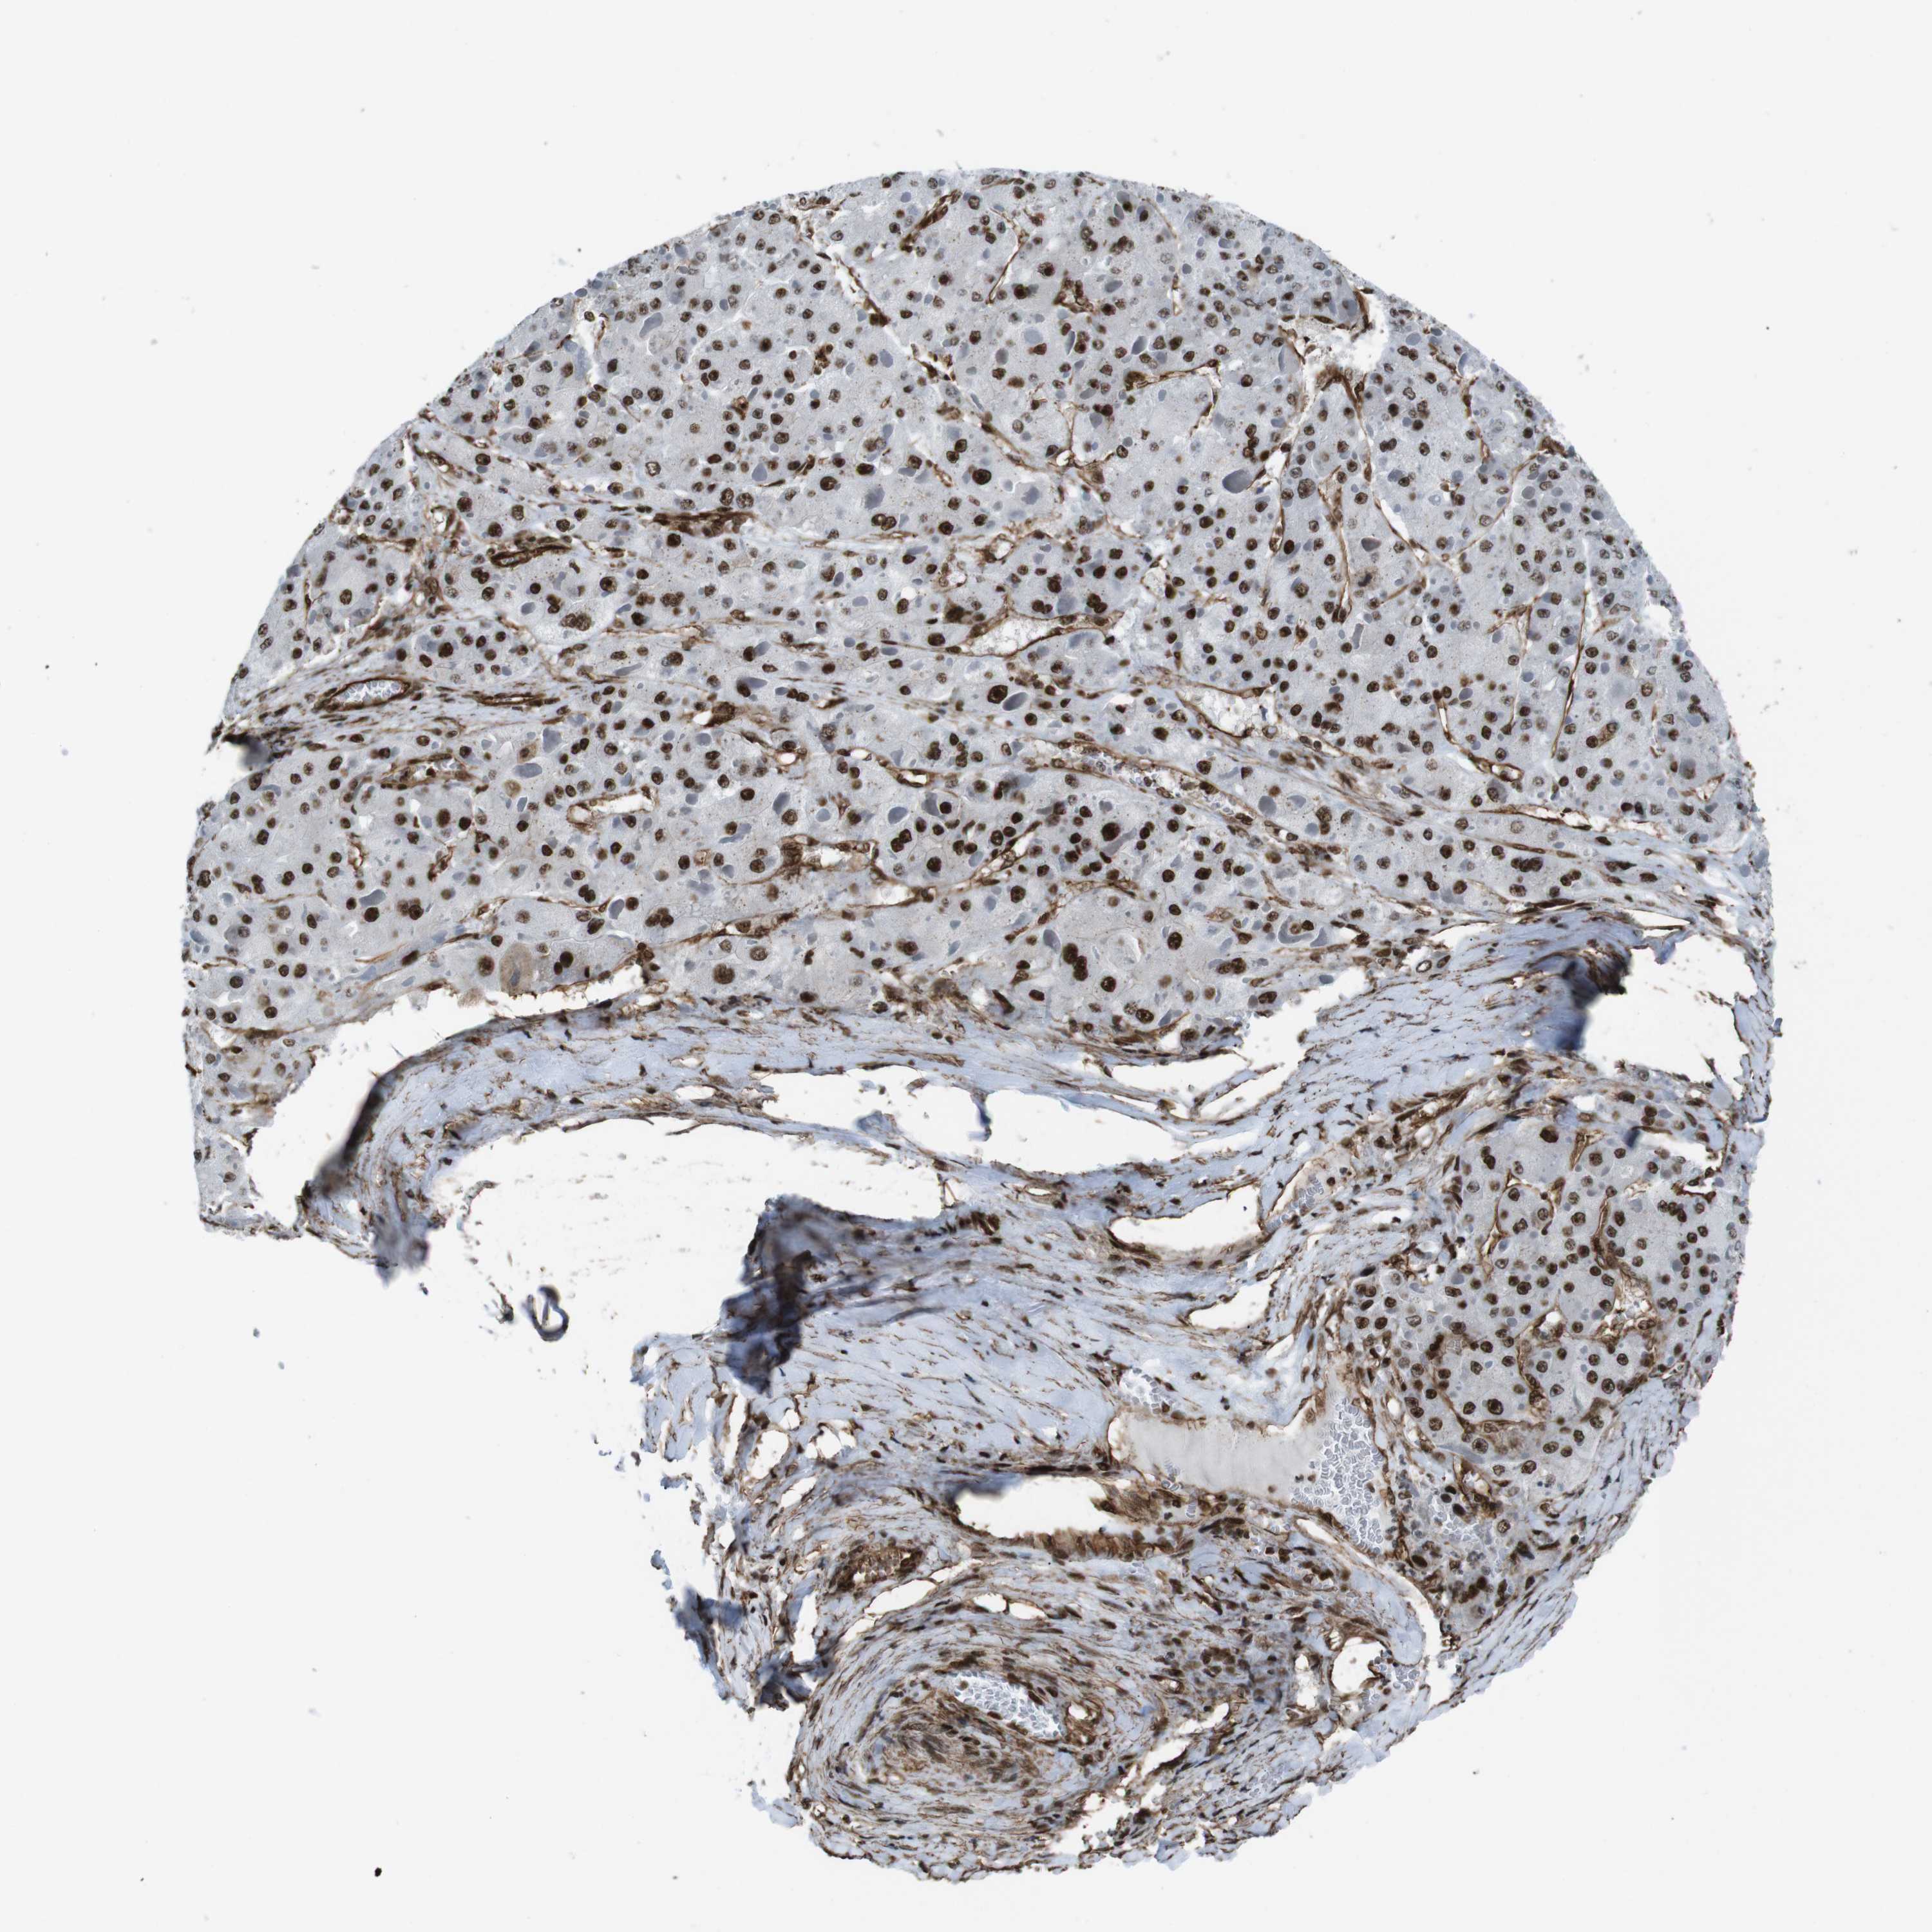

LIVER CANCER - Protein expressioni

A mouse-over function shows sample information and annotation data. Click on an image to view it in a full screen mode. Samples can be filtered based on level of antibody staining by selecting one or several of the following categories: high, medium, low and not detected. The assay and annotation is described here.

Note that samples used for immunohistochemistry by the Human Protein Atlas do not correspond to samples in the TCGA dataset.

Antibody stainingi

Antibody staining in the annotated cell types in the current human tissue is reported as not detected, low, medium, or high, based on conventional immunohistochemistry profiling in selected tissues. This score is based on the combination of the staining intensity and fraction of stained cells.

Each image is clickable and will lead to virtual microscopy that enables deeper exploration of all samples and also displays staining intensity scores, fraction scores and subcellular localization as well as patient and tissue information for each sample.

Antibody HPA041057

Antibody HPA058707

Antibody CAB011532

Staining

High

Medium

Low

Not detected

Intensity

Strong

Moderate

Weak

Negative

Quantity

>75%

75%-25%

<25%

None

Location

Nuclear

Cytoplasmic/membranous

Cytoplasmic/membranous,nuclear

Cholangiocarcinoma

Carcinoma, Hepatocellular, NOS